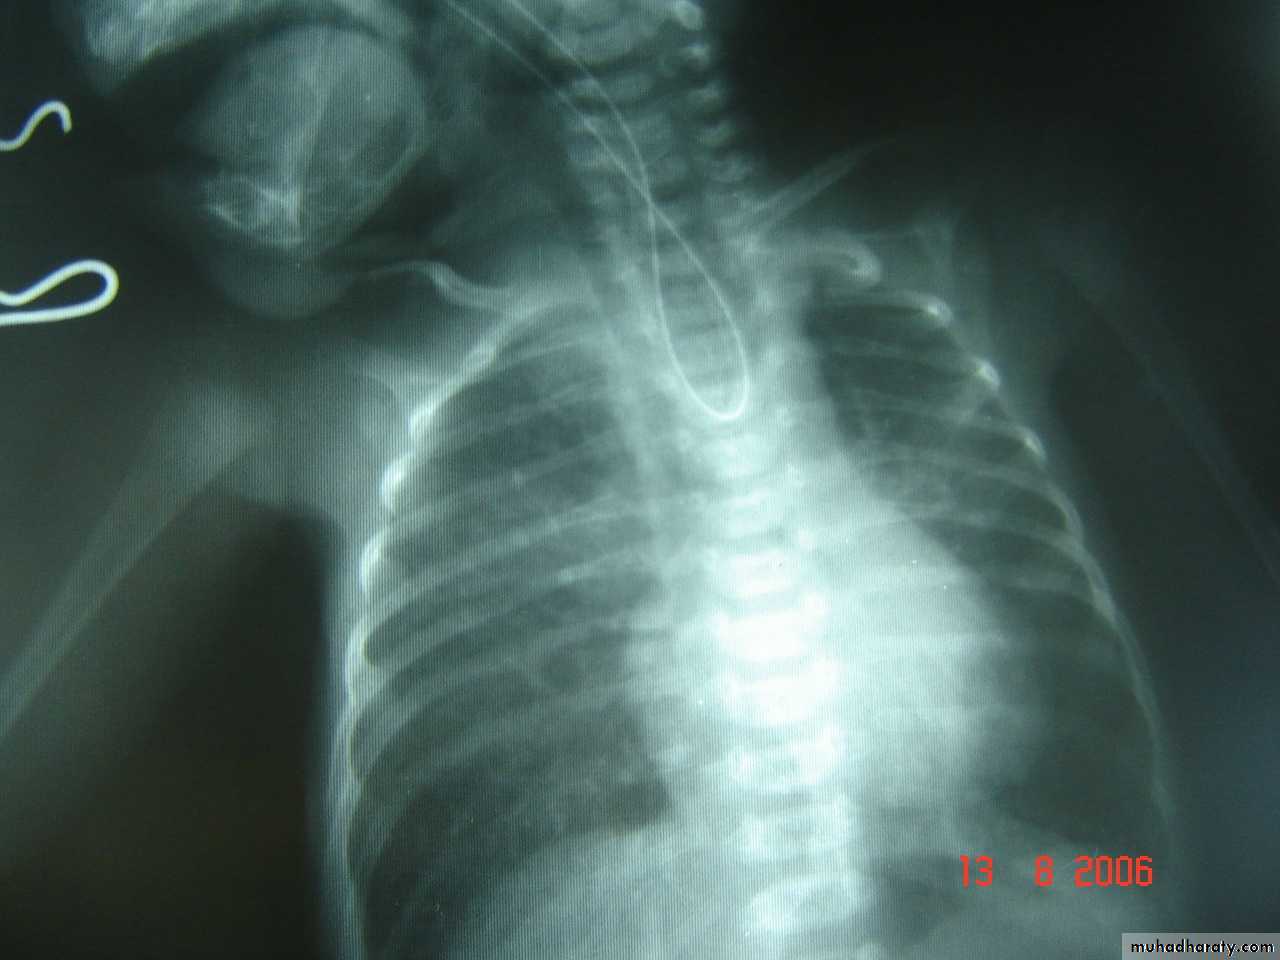

Respiratory Distress in the Newborn

Scaphoid abdomen